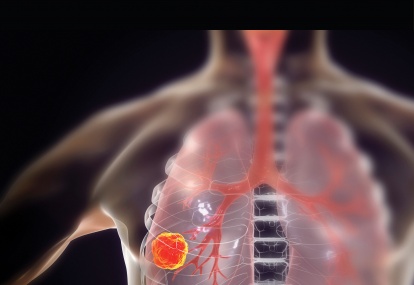

Oncology – non-small cell lung cancer (NSCLC)

Lung cancer remains among the commonest form of cancer in both males and females in Ireland with over 2,500 new cases each year. Unfortunately, a large portion of patients present with inoperable advanced disease and in patients with curable lung cancer – even after surgery, radiotherapy and...